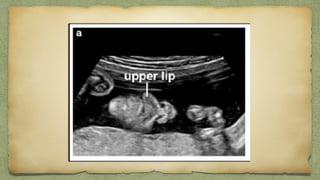

๏ฑNose-Lip view

Cleft lip